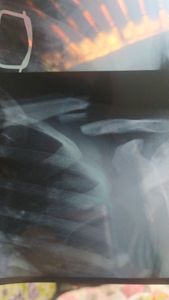

Cirurgia de clavicula

Após um greve acidente de moto, ela teve que parar de trabalhar, agora precisa realizar uma cirurgia de clavicula, pra voltar a seus afazeres normal, porém a família não tem como arcar com os custo e ela já está quase um mês sentindo dores!